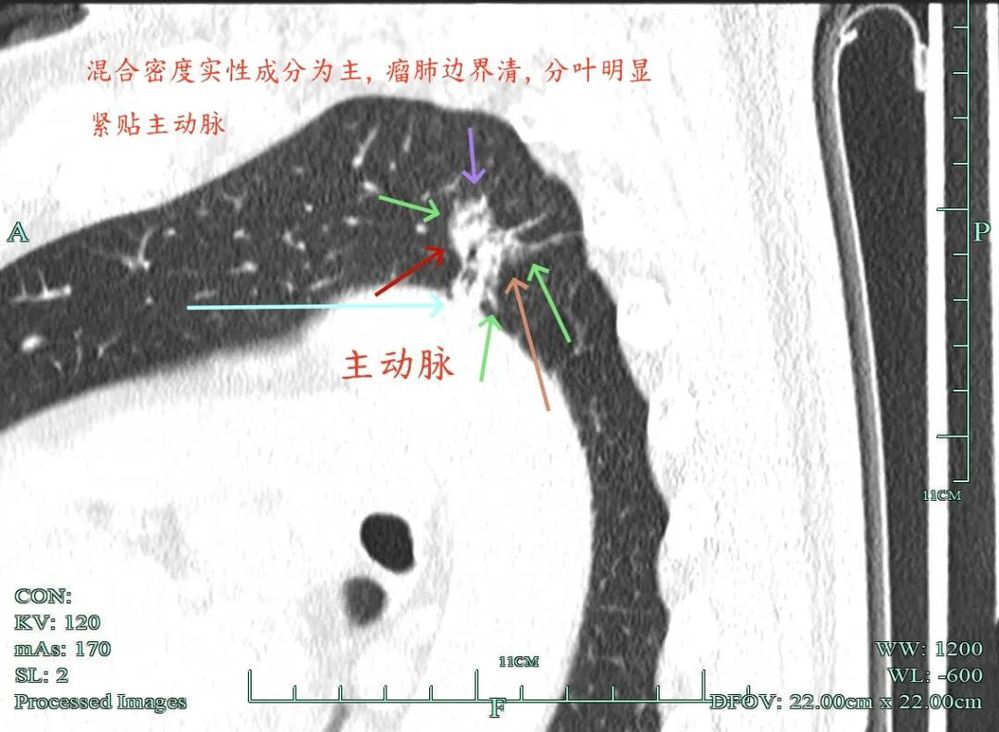

杭州市肿瘤医院影像展示与分析:

右上也有混合密度结节,实性部分缺乏膨胀性与收缩力,磨玻璃成分较淡,也偏糊,但持续存在仍得考虑肿瘤范畴可能性大。

此视角是混合密度,实性为主,贴胸膜近。

左侧主病灶长达三年半时间的随访,当时就是混合密度,整体轮廓较清,随访不好转的话就是要高度警惕恶性的。现在病灶已经明显进展,实性成分增多明显,考虑浸润性腺癌可能性大。肺的粘膜相关B细胞淋巴瘤一般缺乏毛刺征,整体病灶的轮廓与边界会再偏模糊点。但从三年多随访范围增大不多,仍有磨玻璃成分来讲,个人认为已经有转移了的概率可能并高。大概率是中分化浸润性癌可能性大些。右侧病灶也是要考虑浸润性腺癌的,但一是它小些,二是处理要先处理风险更大的一侧,所以右侧病灶拟后续随访叶视其进展再微创干预。